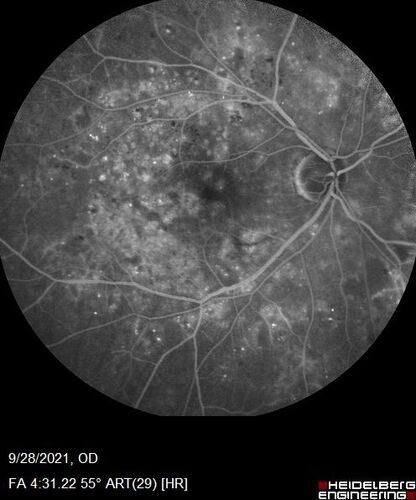

Nonproliferative Diabetic Retinopathy and Good Vision

59 year old man Vision is good.  Just referred following annual eye examination

PMHx: Type II DM, HTN, Cholesterol,

MEDS: Lantus, Metformin, lisinopril, atorvastatin, gabapentin

VA 20/20 OU

2+ NS OU

Observation